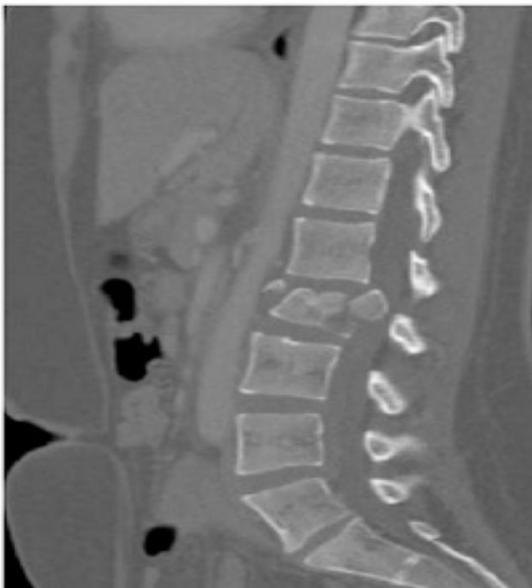

Back ROM & Neurological

This patient has back pain radiating down to his right leg. examine the back

| Special Tests | Structural Assessment Tests | ||

| Adam’s Forward Test | ![]() | ||

| Sacro-iliac stress | Figure of four / or other tests (FABER Patrick Test) | ![]() | |

| Neurological Tests | |||

| Straight leg raise (Lasègue test) | In supine position, raise leg up with knee straight. Look and ask for pain. When pain starts, reduce leg raise, pain disappears. Now passively dorsi-flex ankle to reproduce pain. | ![]() | |

| Femoral stretch | Femoral Stretch Test | ![]() | |